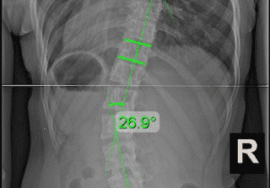

1. الأشعة داخل الحزام (IB-XR)

هي الأشعة التي تُؤخذ أثناء ارتداء الحزام، وتهدف إلى قياس مدى “تصحيح العمود الفقري” بشكل فوري.

كان يُعتقد سابقًا أن هذه الأشعة هي المعيار الأساسي لتقييم نجاح الحزام، حيث اعتبر بعض الأطباء أن نسبة تصحيح تتراوح بين 25% إلى 50% داخل الحزام تشير إلى نتائج جيدة.

لكن المشكلة هنا أن هذه الأشعة لا تعكس الواقع الكامل، لأنها تقيس التأثير الميكانيكي للحزام فقط.